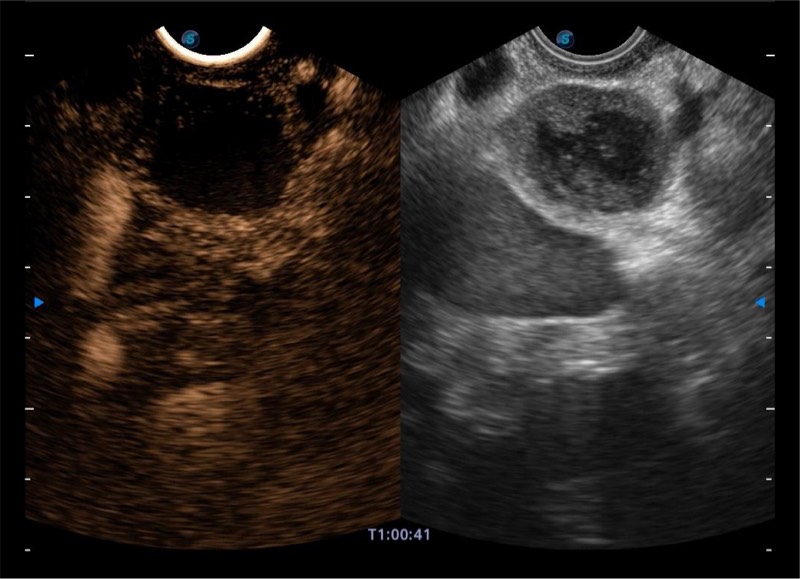

• 搭载百万级CMOS成像技术

• 及自主研发凸阵换能器,

• 可呈现优质的内镜和超声画面

基于二十年的超声技术积累,milan米兰提供了最新一代的独立超声主机,在提供高质量图像的同时满足多学科使用。具备常见多普勒技术并提供弹性成像、声学造影等高端影像技术。新一代传感器具有更强的抗干扰能力并减少图像伪影。